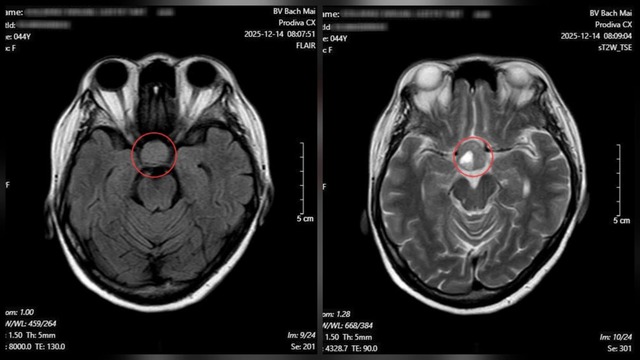

Kết quả chụp cộng hưởng từ (MRI) sọ não cho thấy một khối u tuyến yên kích thước lớn.

Từ những dấu hiệu nghi ngờ, bệnh nhân được chỉ định chụp cộng hưởng từ (MRI) sọ não. Kết quả cho thấy một khối u tuyến yên kích thước lớn (macroadenoma), đo được 26 × 21 mm. Ngay sau đó, người bệnh được chuyển sang chuyên khoa Phẫu thuật Thần kinh để tư vấn điều trị và lên kế hoạch phẫu thuật nhằm tránh các biến chứng nặng nề hơn.